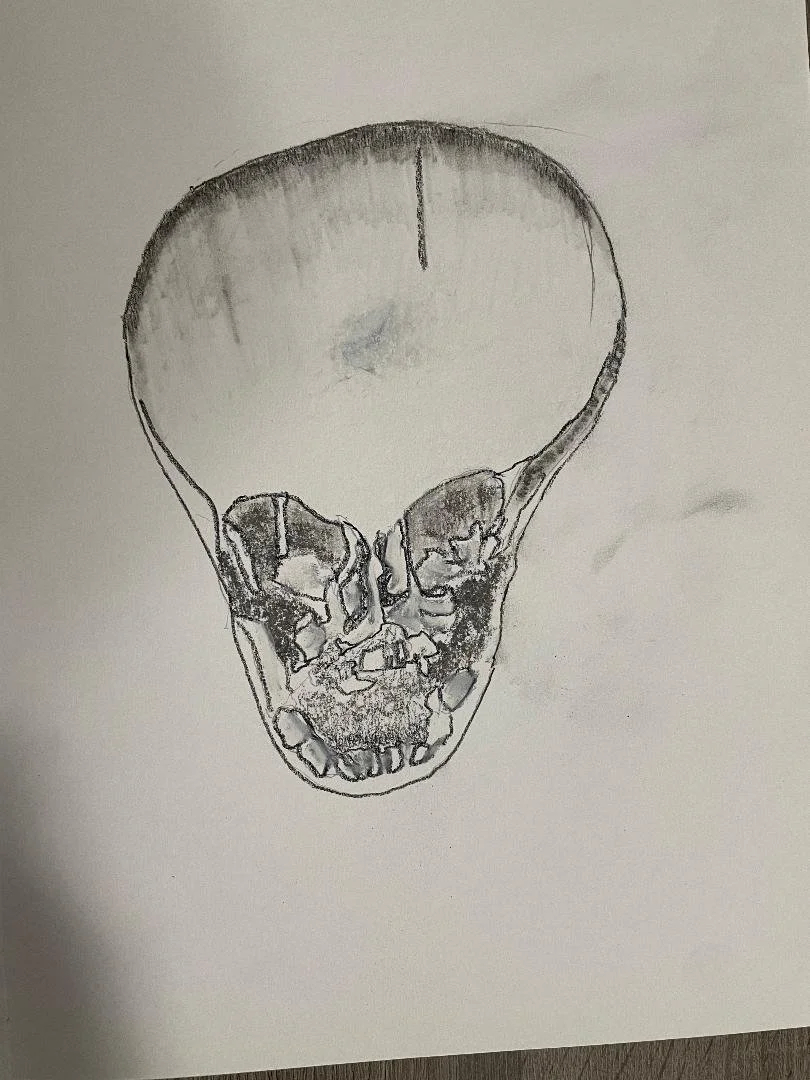

Telangiectatic osteosarcoma - skull